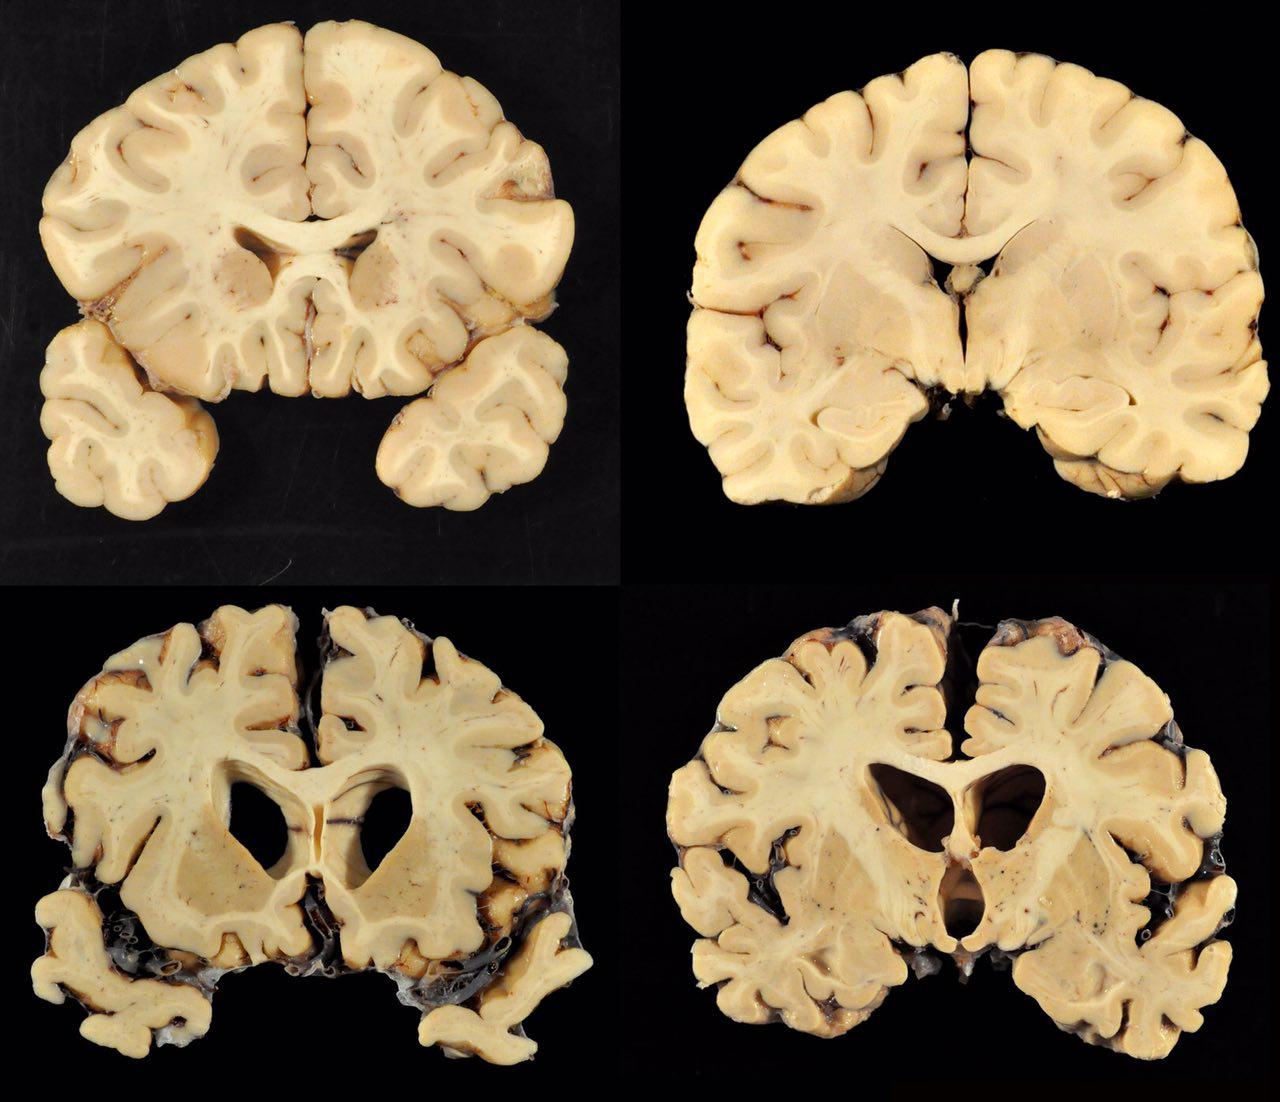

مقایسه مغز افراد سالم (بالا) و بازیکن سابق فوتبال که در ۶۶ سالگی فوت کرده است (پایین)

مقایسه مغز افراد سالم (بالا) و بازیکن سابق فوتبال که در ۶۶ سالگی فوت کرده است (پایین)